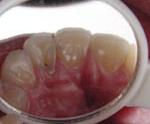

【乳歯の虫歯チェック(左) / 歯の異常を検査(右)】

歯医者に行くのが好きなお子さんはほとんどいないと思います。

歯の予防は大人になっていくときに“とても大切なものなんだ”ということを説明して、無理には治療を行わずに優しく丁寧に行っていきます。